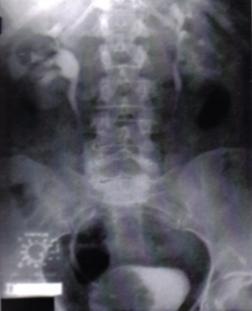

a) Radiografie renovezicala simpla (RRVS) si urografie intravenoasa (UIV)

Fig.8 Imagini lacunare in aria vezicii urinare sugerand tumori vezicale superficiale [51].